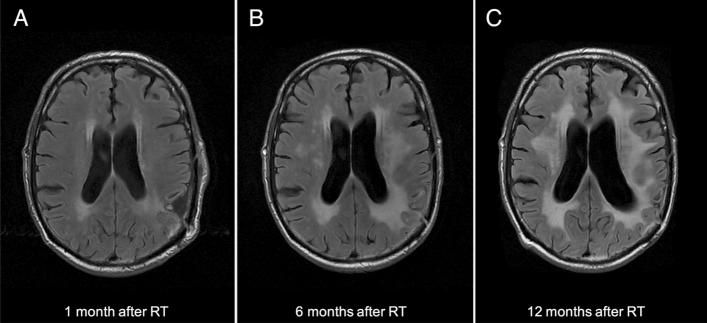

The incidence and risk factors associated with radiation-induced leukoencephalopathy (RIL) in long-term survivors of high-grade glioma (HGG) are still poorly investigated. We performed a retrospective research in our institutional database for patients with supratentorial HGG treated with focal radiotherapy, having a progression-free overall survival > 30 months and available germline DNA. We reviewed MRI scans for signs of leukoencephalopathy on T2/FLAIR sequences, and medical records for information on cerebrovascular risk factors and neurological symptoms. We investigated a panel of candidate single nucleotide polymorphisms (SNPs) to assess genetic risk. Eighty-one HGG patients (18 grade IV and 63 grade III, 50M/31F) were included in the study. The median age at the time of radiotherapy was 48 years old (range 18-69). The median follow-up after the completion of radiotherapy was 79 months. A total of 44 patients (44/81, 54.3%) developed RIL during follow-up. Twenty-nine of the 44 patients developed consistent symptoms such as subcortical dementia (n = 28), gait disturbances (n = 12), and urinary incontinence (n = 9). The cumulative incidence of RIL was 21% at 12 months, 42% at 36 months, and 48% at 60 months. Age > 60 years, smoking, and the germline SNP rs2120825 (PPARg locus) were associated with an increased risk of RIL. Our study identified potential risk factors for the development of RIL (age, smoking, and the germline SNP rs2120825) and established the rationale for testing PPARg agonists in the prevention and management of late-delayed radiation-induced neurotoxicity.

放射性脑白质病(RIL)在高级别胶质瘤(HGG)长期幸存者中的发病率和相关风险因素仍研究甚少。我们对在我院接受局部放疗的幕上 HGG 患者的机构数据库进行了回顾性研究,这些患者的无进展总生存期(PFS)>30 个月,并且有可利用的种系 DNA。我们对 T2/FLAIR 序列上的脑白质病的 MRI 扫描进行了复查,并对脑血管危险因素和神经症状的医疗记录进行了审查。我们研究了一组候选单核苷酸多态性(SNP),以评估遗传风险。共纳入 81 例 HGG 患者(18 例 IV 级和 63 例 III 级,50 例男性/31 例女性)。放疗时的中位年龄为 48 岁(18-69 岁)。放疗完成后的中位随访时间为 79 个月。在随访期间,共有 44 例(44/81,54.3%)患者发生 RIL。在这 44 例患者中,29 例(29/44)出现了皮质下痴呆(n=28)、步态障碍(n=12)和尿失禁(n=9)等一致的症状。RIL 的累积发生率为 12 个月时为 21%,36 个月时为 42%,60 个月时为 48%。年龄>60 岁、吸烟和种系 SNP rs2120825(PPARg 基因座)与 RIL 风险增加相关。我们的研究确定了 RIL 发展的潜在风险因素(年龄、吸烟和种系 SNP rs2120825),并为测试 PPARg 激动剂在预防和管理迟发性放射性神经毒性方面提供了依据。